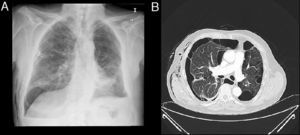

La válvula se introduce mediante un catéter a través del canal de trabajo del broncoscopio y al liberarla se autoexpande, anclándose a la mucosa bronquial (fig. 2A y B).

Durante todo el procedimiento se monitoriza cuidadosamente la profundidad de la anestesia y las constantes vitales, y al finalizar su colocación se realiza una radiografía de tórax (fig. 3A y B), o una TC si fuera necesario (fig. 3C y D) para descartar complicaciones, constatar la reexpansión pulmonar y su correcto enclave.

A)Radiografía de tórax con válvulas IVB en lóbulo superior derecho. B)Detalle de la radiografía de tórax con válvulas IBV en lóbulo superior derecho. C)TC de tórax en paciente con enfisema bulloso y válvula IBV colocada en B2 derecho (señalada por fecha). D)TC de tórax en paciente con enfisema bulloso y válvula IBV colocada en B1 derecho (señalada por flecha). Paciente con neumotórax derecho y enfisema pulmonar (paciente n.¿ 5).